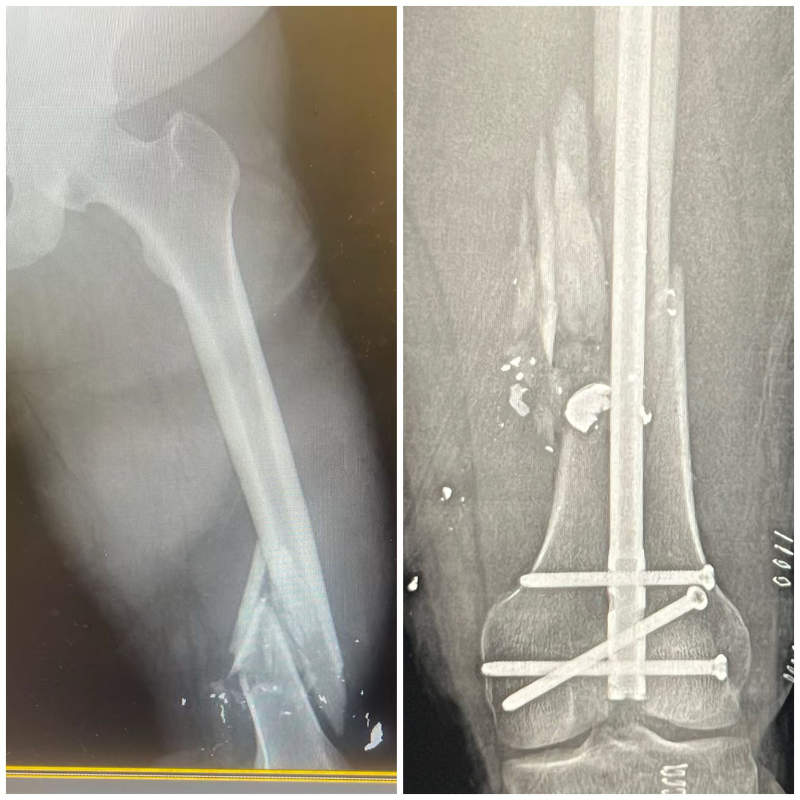

Internal and External Fixation Techniques

Internal Fixation:

This involves using specialized implants like plates, screws, rods (intramedullary nails), or wires to stabilize the broken bone fragments from within. These devices hold the bone in proper alignment while it heals.

Complex Fracture Reconstruction and Non-Union Treatment

Some fractures are particularly challenging, such as those involving multiple fragments, significant bone loss, or those that fail to heal (non-unions). Dr. Arroyo has extensive experience in complex fracture reconstruction, utilizing advanced techniques like bone grafting, specialized plating systems, and biologic agents to salvage limbs and restore function in even the most difficult cases.

xray fixed injury Orthoedge